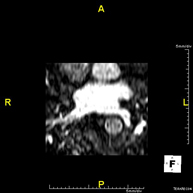

- Colangiopancreato-RM (RM Páncreas, vesícula y vía biliar)

Prueba diagnóstica no invasiva que consiste en la obtención de imágenes de alta definición anatómica de los conductos de drenaje pancreático (principalmente el conducto de Wirsung ), de la vía biliar y de la vesícula biliar mediante el empleo de un campo electromagnético y ondas de radio (con un emisor y un receptor). No utiliza radiación ionizante. Requiere unas 6 horas de ayuno previo, ya que al no haber ingerido nada, la bilis y los jugos pancreáticos se habrán acumulado, permitiendo una mejor definición anatómica de los mismos. En algunas ocasiones se requiere el uso de contraste paramagnétrico (Gadolinio) para caracterizar las lesiones. Está especialmente indicada en pacientes con sospecha de piedras en el conducto de drenaje de la vía biliar o colédoco, enfermedad a nivel de la unión de los conductos biliares y los pancreáticos, pacientes con pancreatitis de repetición, dolor abdominal con probable origen biliar o pancreático, como estudio anatómico pre-quirúrgico, etc.